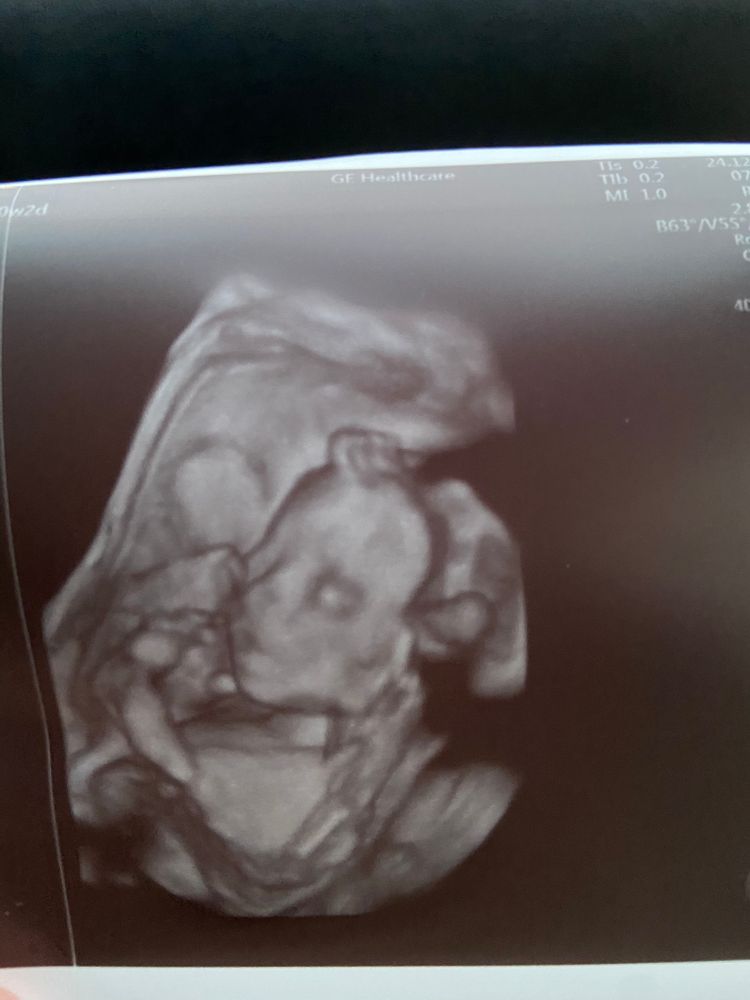

20 недель и 2 дня второй скрининг

сохраню на память. Ведь это был особенный день. Мы впервые на узи увидели нашу девочку в 3д… в этот день дети старшие выступали на отчетном концерте по бальным танцам и нам надо было успеть съездить на узи и приехать на концерт:). На узи ездил муж, дети готовились к выступлению.